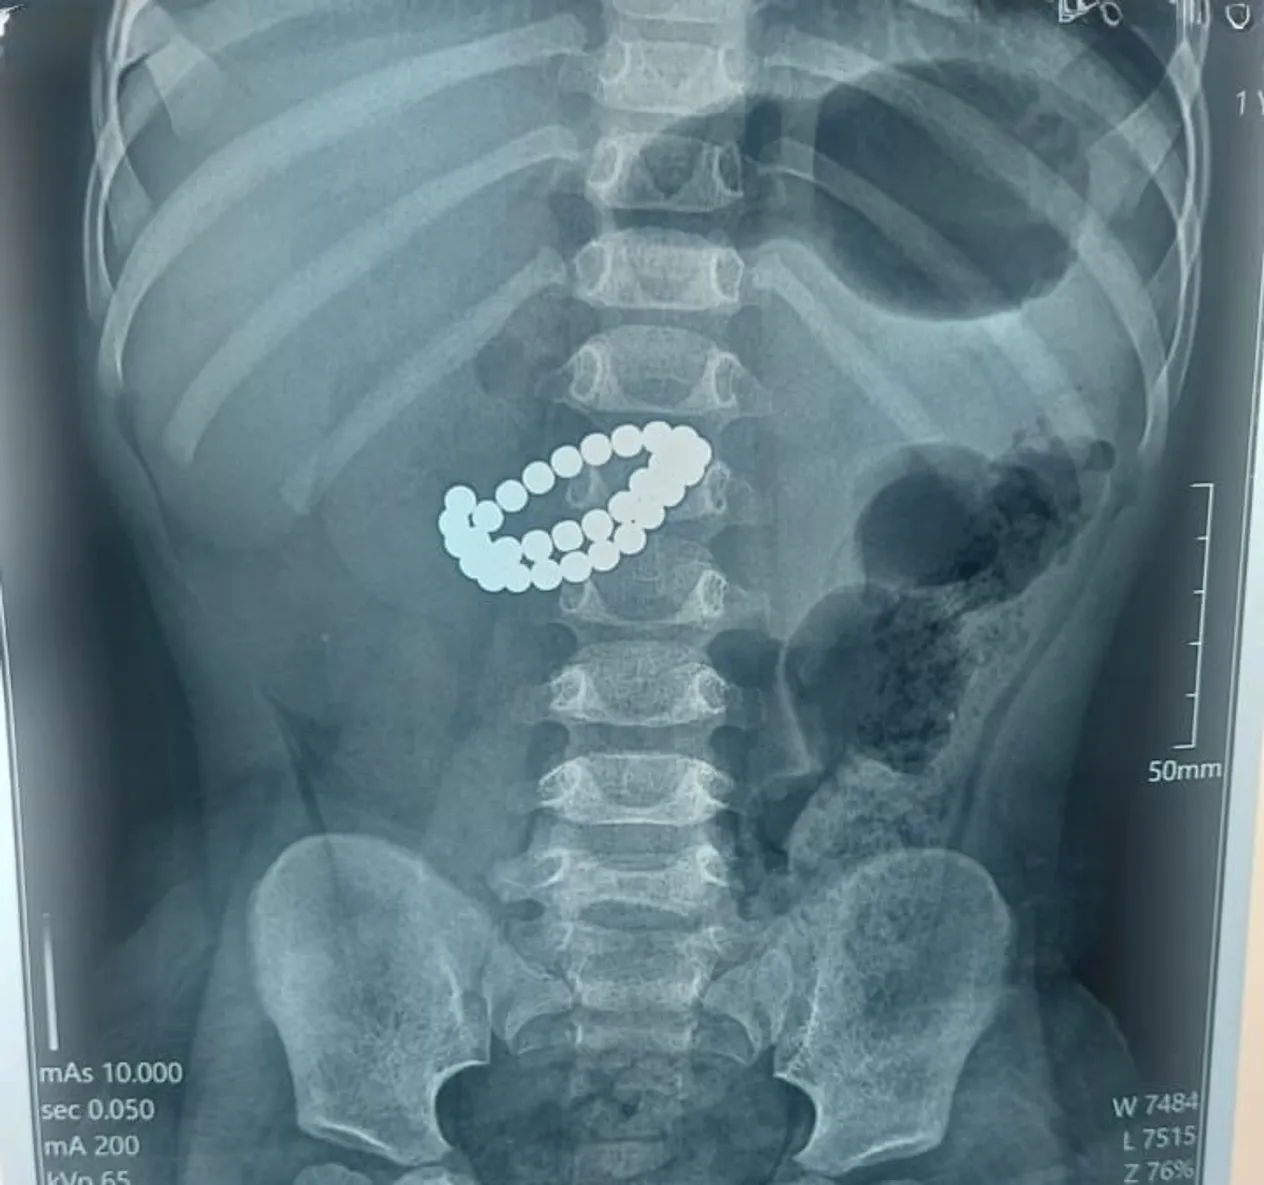

В центре детской неотложной медицинской помощи Алматы экстренно прооперировали малыша, который проглотил 31 магнит, сообщает QazMonitor.

Малыш поступил в приемное отделение в крайне тяжелом состоянии. После обследования у него диагностировали инородные тела в кишечнике, множественные перфорации тонкой кишки и диффузный каловый перитонит.

Единственным шансом на спасение стала срочная хирургическая операция. Медики выполнили срединную лапаротомию с ревизией органов брюшной полости, извлекли магниты, ушили перфорации, провели санацию и дренирование, а также трансанальную интубацию кишечника.